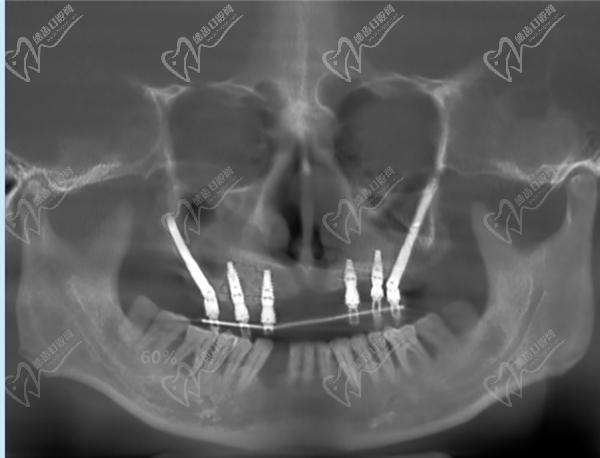

醫(yī)生團隊:公辦醫(yī)院名家楊朝暉每月坐診(中 山大學孫逸仙紀念醫(yī)院),種植牟家云院長,種植外科醫(yī)療20多年,精通各類高難度種植如 all-on-4,穿顴穿翼。